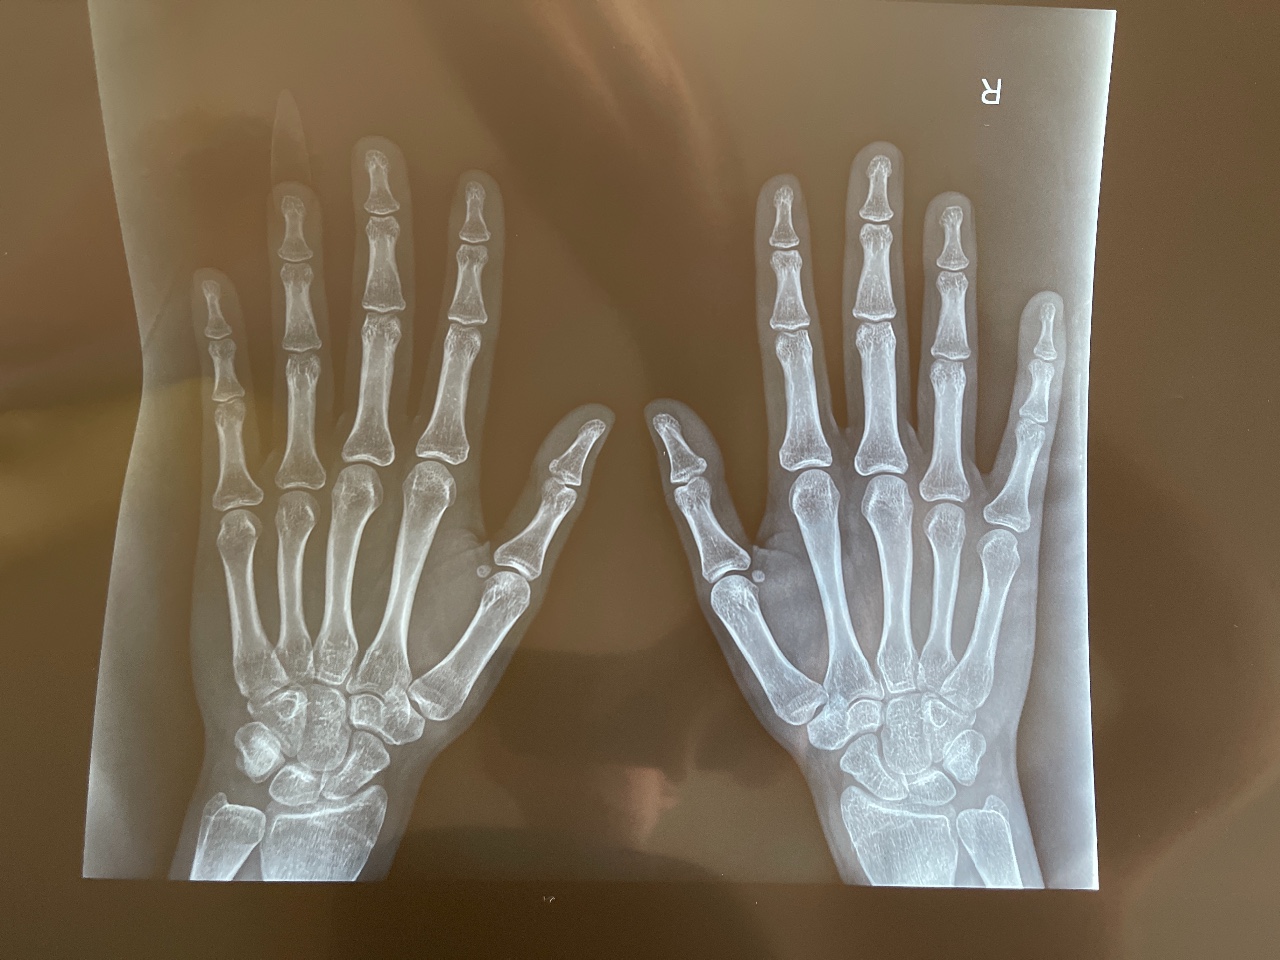

Зоны роста закрыты

Зоны роста закрыты 141 фотографий